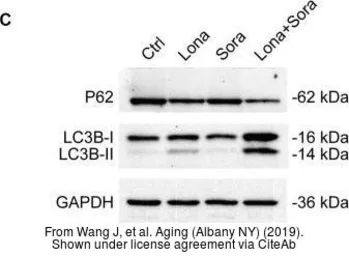

The data was published in the Cancer Med in 2020. PMID: 32324343